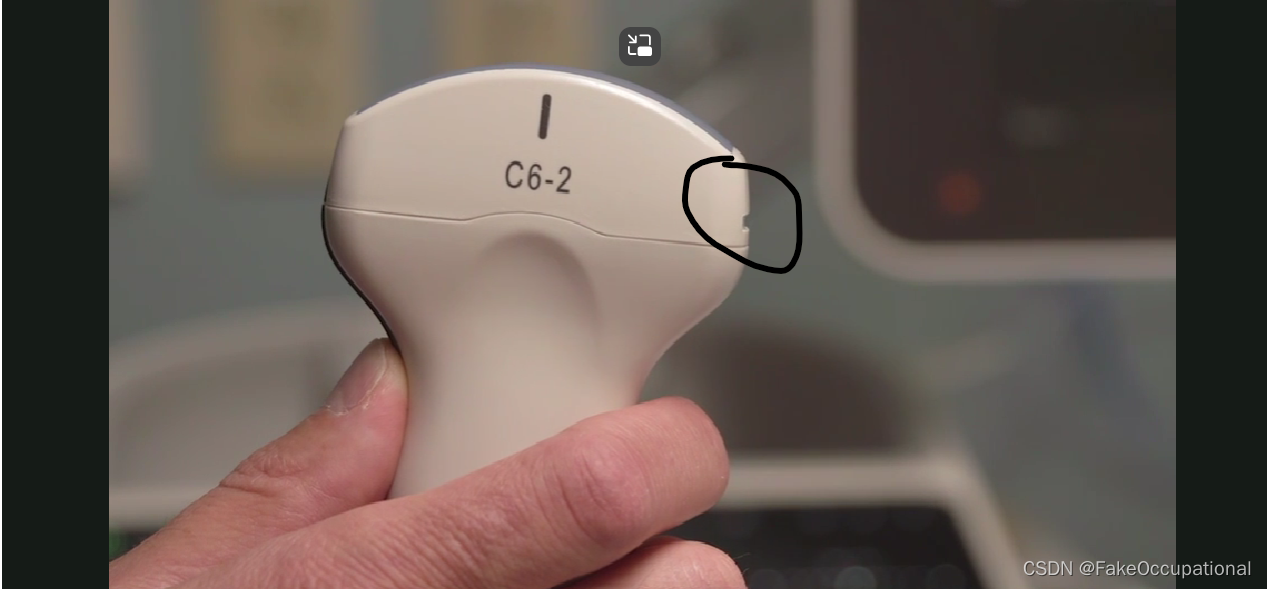

- 探头上是有方位标记点的,显示器中方位点在左侧。标准方向放置后,患者的右侧应该出现在显示器的左侧。探头一侧的探头方向标记应面向患者的右侧(如果探头纵向定向,则朝向头侧),并且超声监视器上的标记点位于超声监视器的左上角。